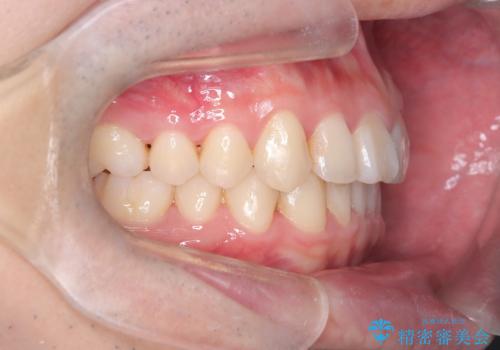

- 前歯が出ていることを主訴に来院されました。

歯列の幅が狭かったため、横に広げながらスペースを作り、叢生の改善を行いました。

左側の犬歯関係も治療前より良い状態で治療を完了することができました。

今回は臼歯部の遠心移動を行うために2級ゴムを使用しています。